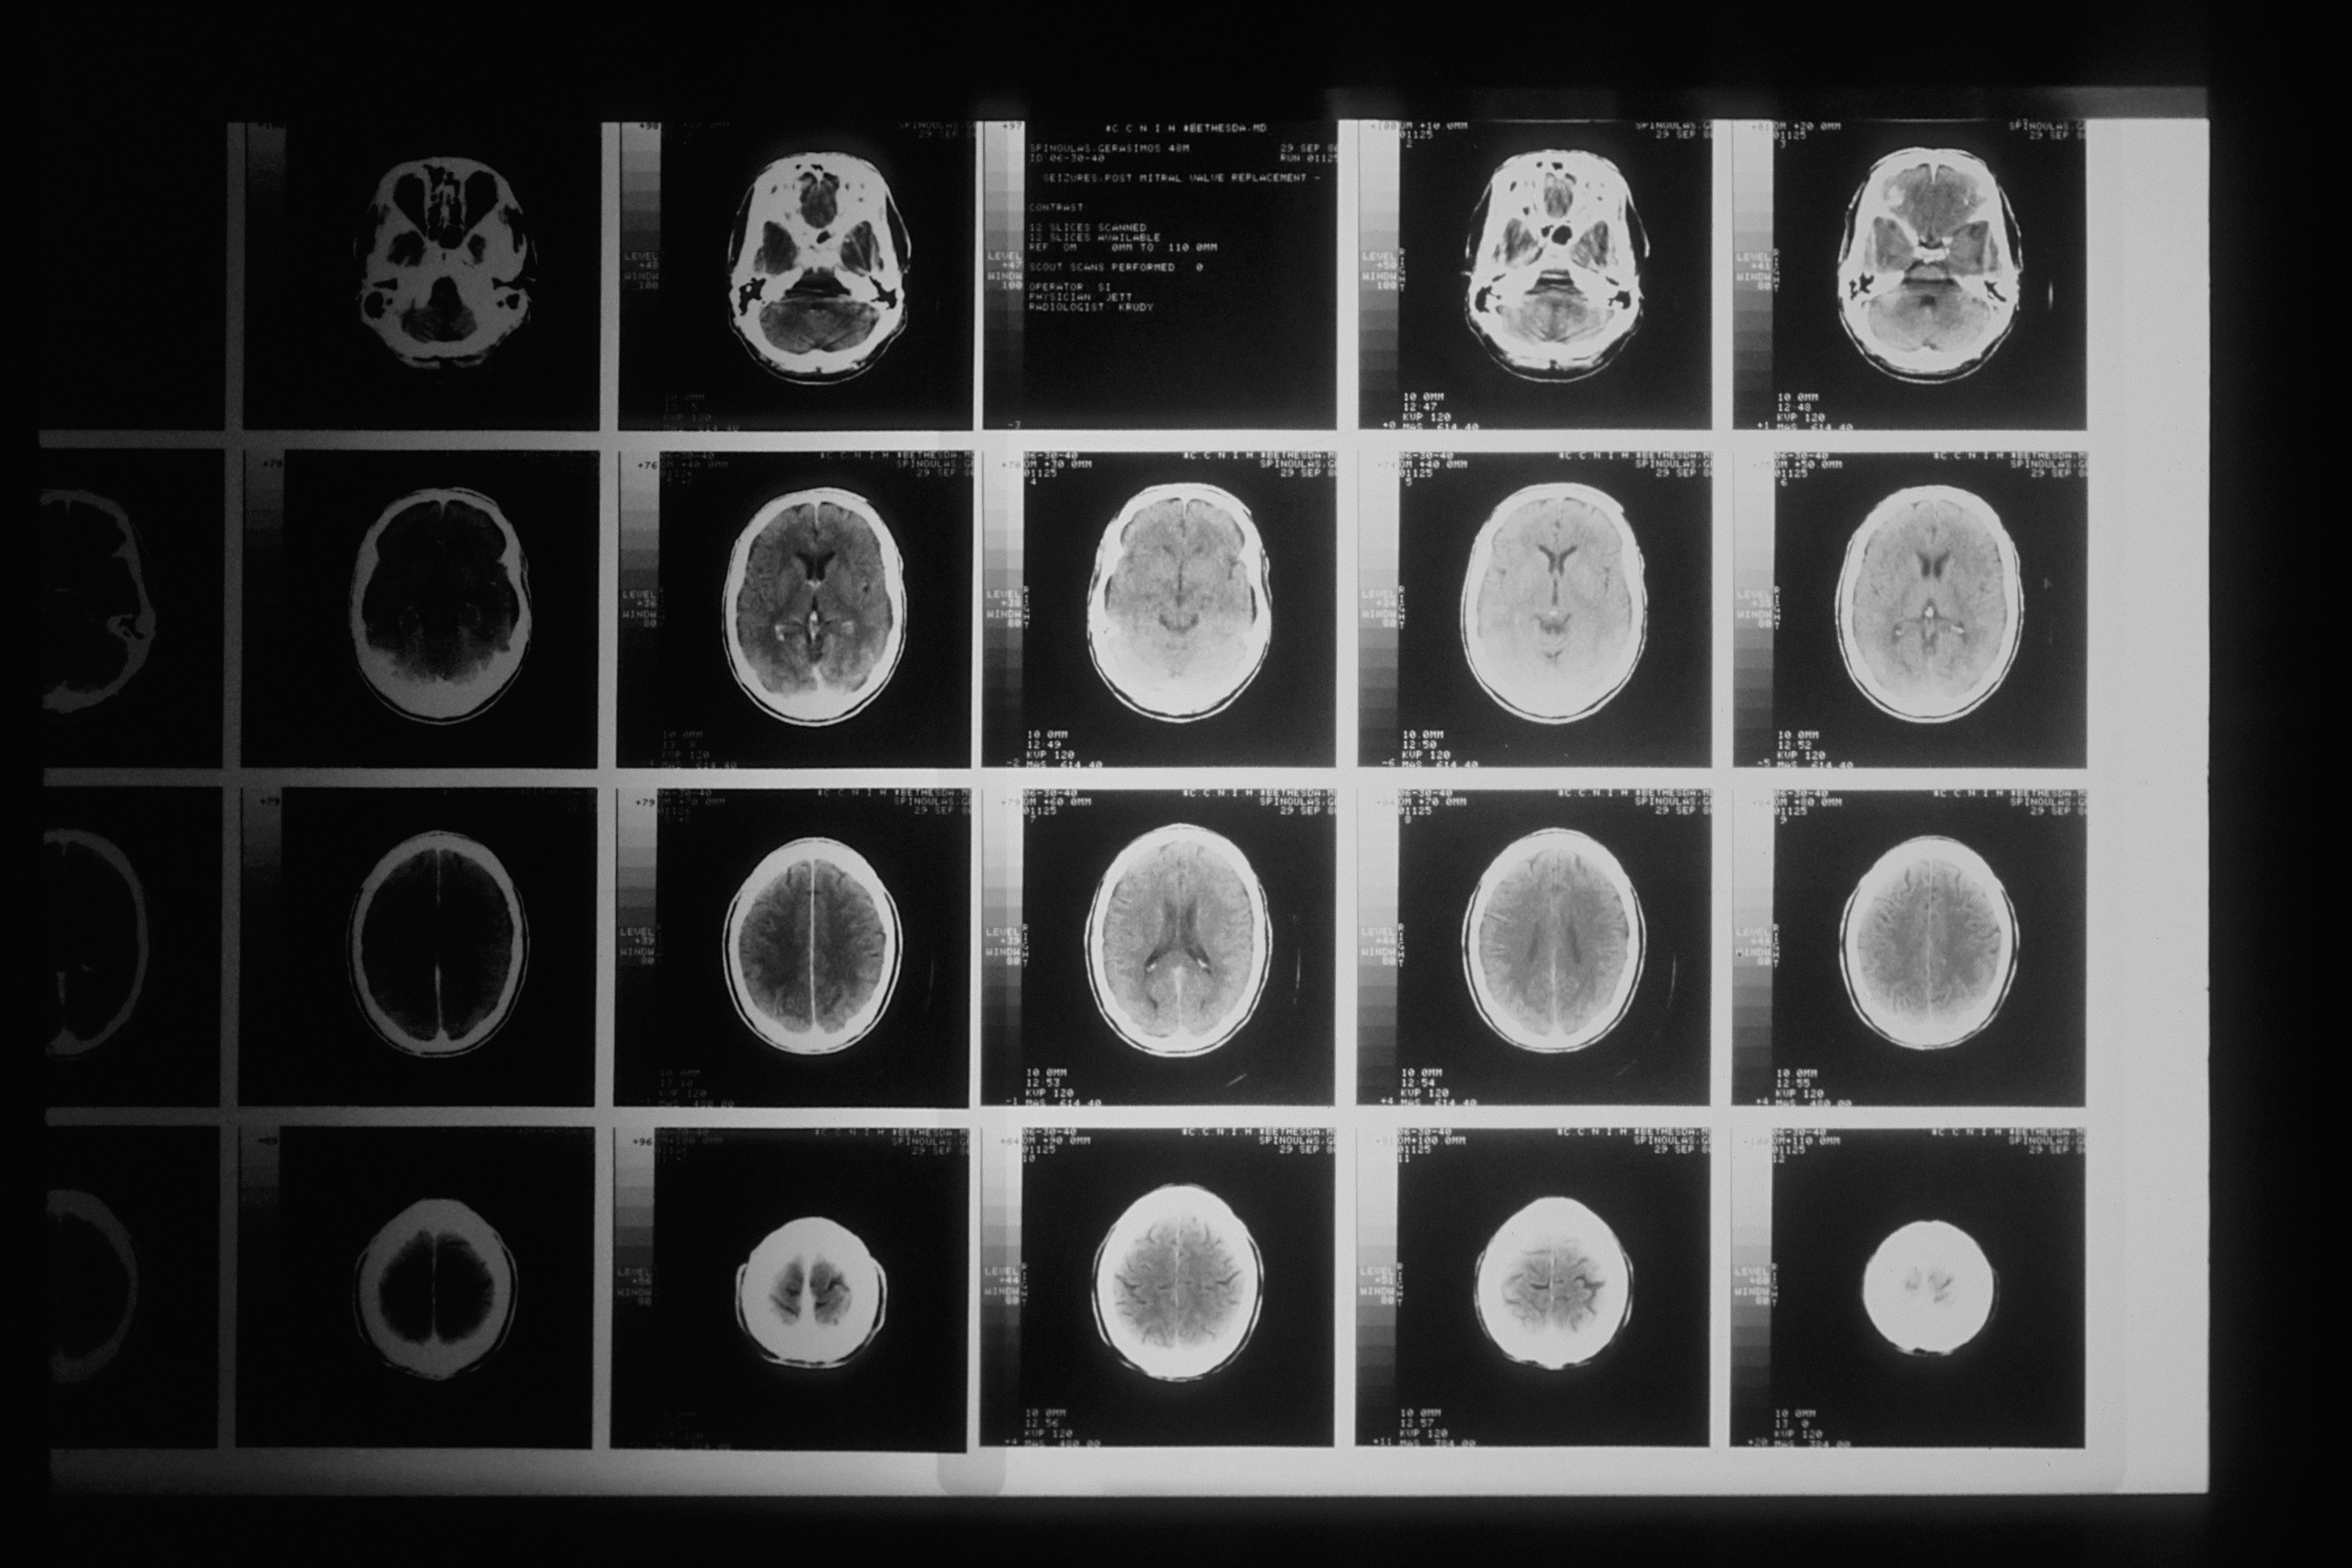

In the field of Physics, I’ve delved deep into understanding the fundamental laws that govern our universe. My contributions to groundbreaking research have focused on neuroscience and brain imaging, utilizing the power of near-infrared spectroscopy to unravel the intricacies of the human brain. Additionally, I’ve brought my expertise to the realm of non-destructive imaging in the terahertz class, where I’ve played a pivotal role in designing and validating critical electronic systems. This dedication to the field led to my co-authorship of international conference papers in accelerator research, highlighting my commitment to pushing the boundaries of scientific discovery.